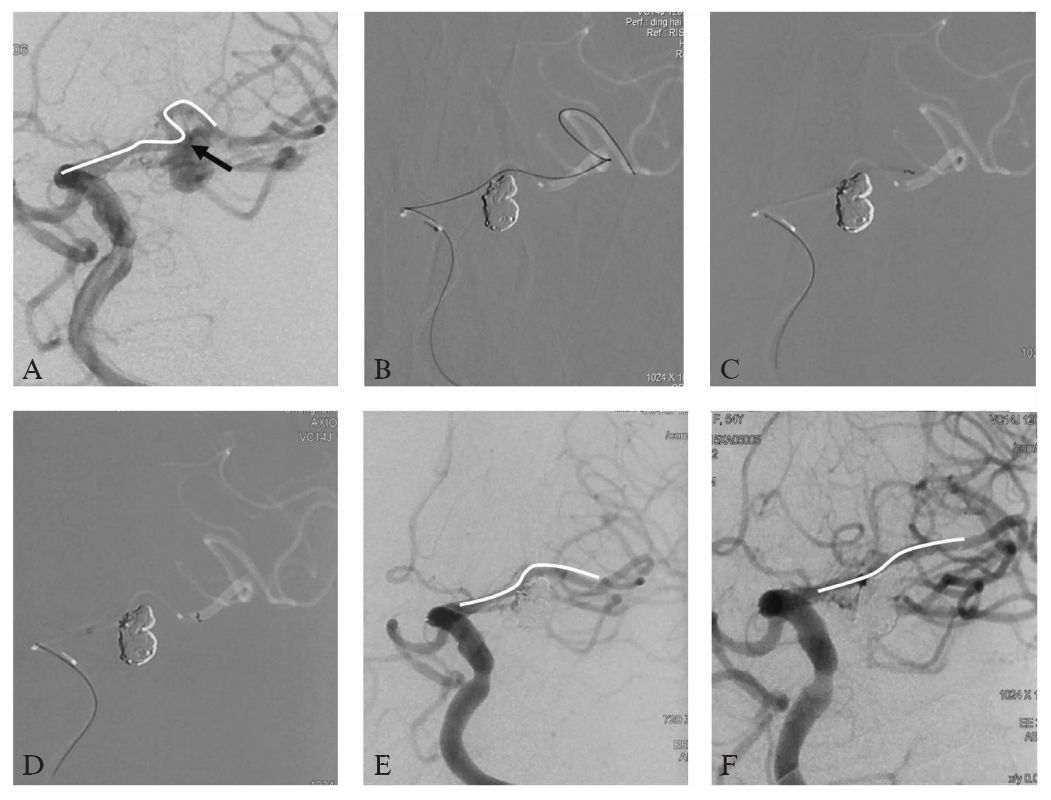

DSA:左侧颈内动脉造影显示左侧大脑中动脉分叉部相对宽颈动脉瘤,动脉瘤呈分叶状,且同时累及上干和下干(图10-2A、B);三维旋转造影重建显示载瘤动脉在瘤颈处成约60°的锐角,主要累及上干,下干自瘤颈处发出。标记测量:动脉瘤最大径约9.7 mm,瘤颈约2.8 mm,两分叶小泡大小分别为6.28 mmX5.26 mm,4.1 mmX3.39 mm,载瘤动脉近远端直径分别为2.03 mm及1. 65 mm(图10-2C、D)。

图10-2 患者术前DSA及三维重建影像

A,B:工作角度造影显示左侧大脑中动脉分叉部宽颈动脉瘤.动脉瘤呈分叶状,且同时累及上干和下干;

C:三维旋转造影重建显示M2,M3在瘤颈处成明显约60°的锐角,下干自瘤颈处发出

鉴于血管迁曲,支架导管直接导向远端较为困难。我们首先使用了双微导管技术,2根微导管通过塑形分别超选入动脉瘤的两个子囊内(图10-3A、B),于大囊及小囊内分别填入Axium 3D 6 mm/15 cm及Axium 3D 4 mm/8 cm弹簧圈各1枚顺利成篮,而后依次填入Axium 3D 3 mm/8 cm,2 mm/4 cm,Axium Helix 2 mm/8 cm,Axium 3D 2 mm/4 cm,2 mm/4 cm,Axium Helix 2 mmX 6 cm,2 mm/4 cm,2 mm/2 cm,1.5 mm/2 cm共11枚弹簧圈,期间通过反复调整微导管位置、张力控制弹簧圈的填塞部位,保持载瘤动脉及其分支的通畅(图10-3E、F)。

图10-3 患者弹簧圈栓塞过程的DSA影像

A~D:动脉瘤术中操作示意图,2根微导管通过塑形分别超选入动脉瘤的两个子囊内,通过反复调整微导管位置、张力控制弹簧圈的填塞部位;白色及黑色线所示为动脉瘤上下子囊微导管超选示意(A,B)及填塞效果示意(C,D),图B因对比度需要白色曲线改用虚线代替;E~G为术后造影图,显示动脉瘤栓塞后载瘤动脉及分支保持通畅

因动脉瘤瘤颈主要累及上干,且上干粗大,成角更大,故选择大脑中动脉M1至M2上干行支架成形术。在动脉瘤内弹簧圈支撑下,Echelon 10微导管顺利通过上干与M1段成角处(图10-4A),到达上干远端;因远端血管迁曲,微导管难以走远,故考虑植入Solitaire支架。微导管路图下,使用Transcend 300 Floppy交换导丝,交换Rebar 18微导管到位(图10-4B、C),释放Solitaire 4 mmX20 mm支架1枚(图10-4D),术后造影显示动脉瘤致密栓塞,上下干通畅(图10-4E)。与术前造影(图10-4A)相比,上干明显变直,曲度减小。

图10-4 患者支架植入过程图示及术后、随访造影

A:白色曲线为微导管超选示意图,注意大脑中动脉上干与M1段处成角明显(黑色箭头),该处弹簧圈予以相应支撑使得微导管得以超选远端;

B:Echelon 10微导管路图后Floppy交换导丝到达大脑中动脉M3段;

C:Rebar 18微导管交换到位;

D:Solitaire支架顺利释放,覆盖瘤颈;

E:术后即刻工作角度造影,显示动脉瘤致密栓塞.上下干通畅,与术前造影(A)相比,上干明显变直,曲度减小(白色曲线);

F:术后6个月后DSA复查结果,动脉瘤完全不显影,分支通畅,白色曲线所示大脑中动脉上干,与术前相比(A)血管曲度进一步变直